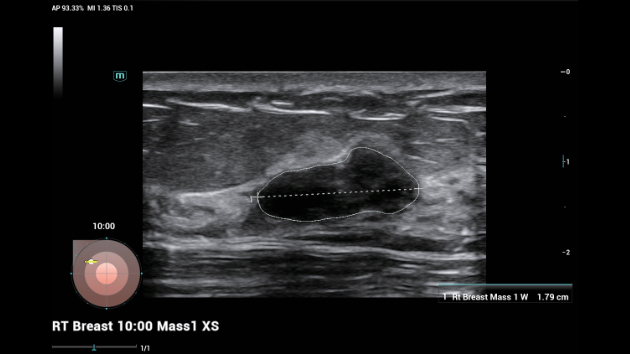

Ongeacht of u werkzaam bent in een ziekenhuis of kliniek, of uw vaardigheden aanscherpt op het gebied van algemene beeldvormingstoepassingen, vrouwengeneeskunde of cardiovasculaire specialismen, in deze serie vindt u zeer krachtige hulpmiddelen waarmee u aan kop kunt blijven.

Uitgebreide?oplossingen voor beeldvorming aangestuurd door ZST?+

Het ZST+?platform is een buitengewone innovatie en revolutie in de wereld van echografie. Het transformeert echografiegegevens van conventionele bundelvorming naar kanaalgegevensverwerking. Het overwint de traditionele afweging tussen ruimtelijke resolutie, temporele resolutie en weefseluniformiteit, en levert een uitzonderlijke beeldkwaliteit voor oneindige beeldvormingsoplossingen met non-stop verbeteringen.